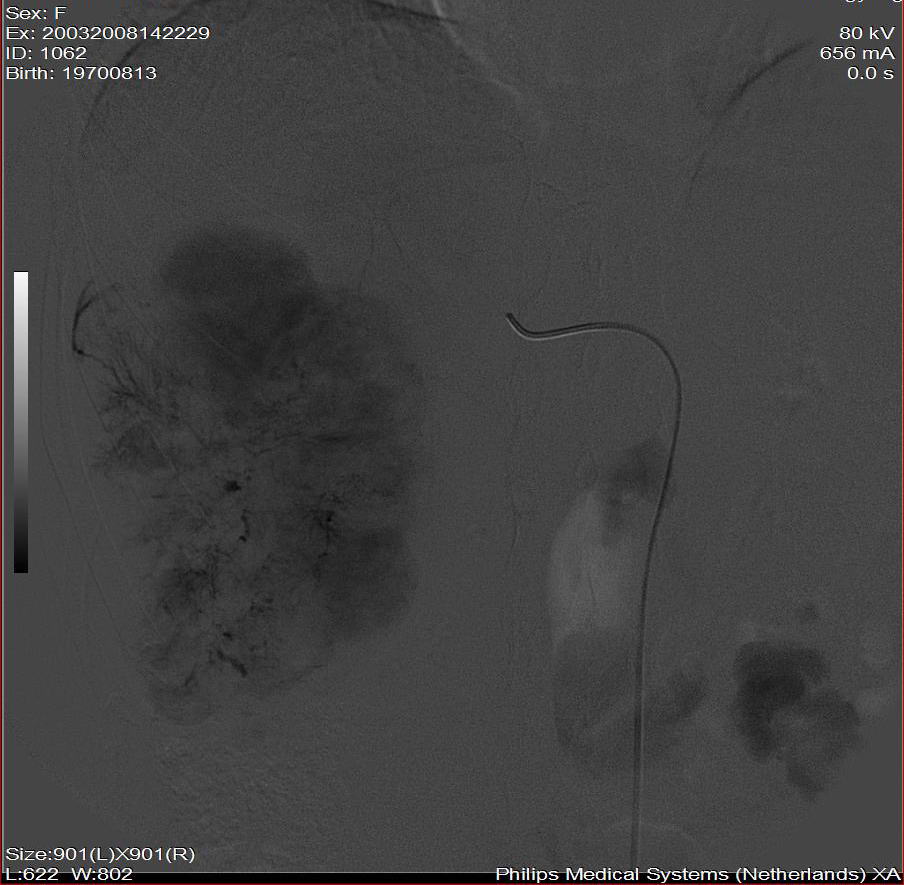

标题: DSA0138:F38Y,肝脏病变

第二次(50天后)

栓塞的非常理想。

巨块型肝癌介入术后,肝左叶有转移吗(第二次进行肝左动脉栓塞了吗?)